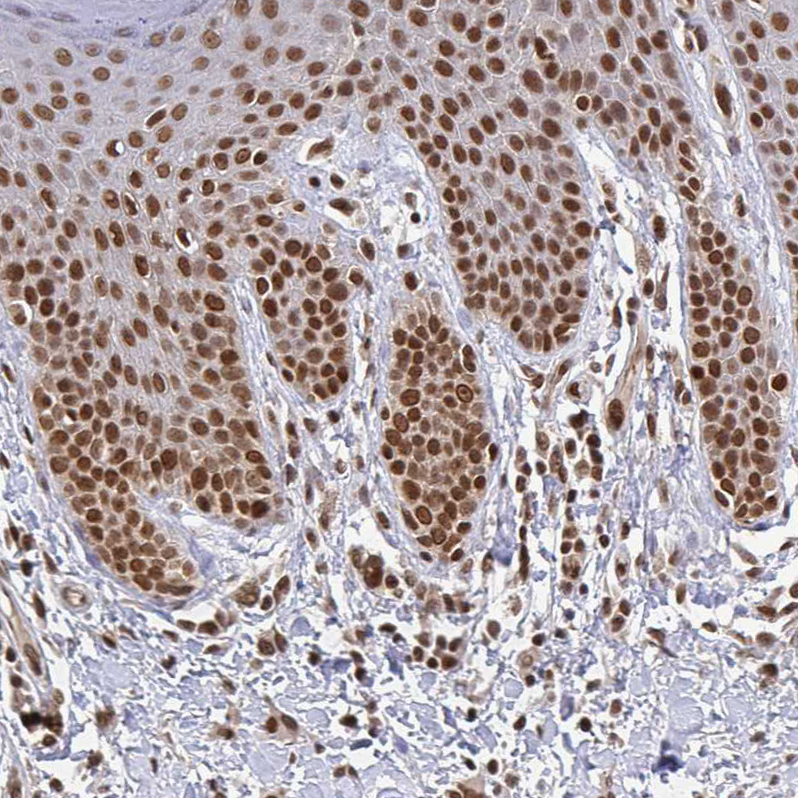

Immunohistochemical staining of human testis shows strong nuclear positivity in cells in seminiferous ducts.